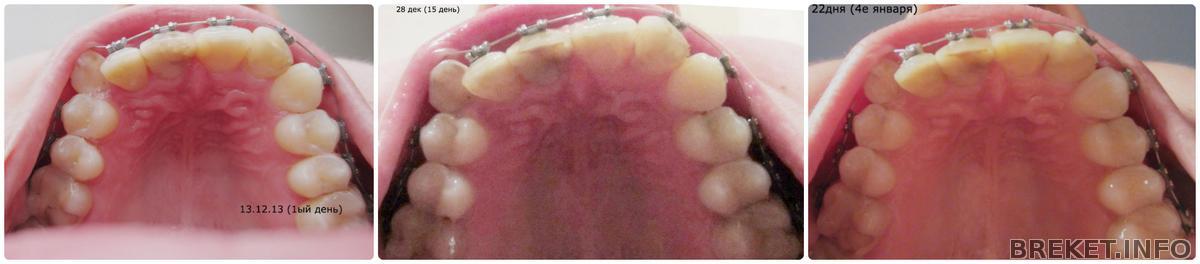

Что касается, непосредственно, прогресса в движении,-он чуточный. Вижу,что выпрямилась дуга немного, и похоже, изгиб на клыке стал малость плавнее,хотя может у меня глюки ![]()

Ну и коллажики с интервалом в неделю

Не знаю как вы, а я вижу, что клык с правой стороны подвинулся. Приглядитесь повнимательней))

А я думала,что мне показалось

Он будто задвинулся вовнутрь,видно на снимке снизу по дуге)) ![]()

Видишь на ранних сроках.. еще о важно попасть в ракурс. Мне кажется в 1.5 месяца мы уже увидим что то особенное у тебя с зубами. А сейчас лишь хорошая гигиена и о Боже мой... единички.. там дуга вытянулась! Как я так проглядела